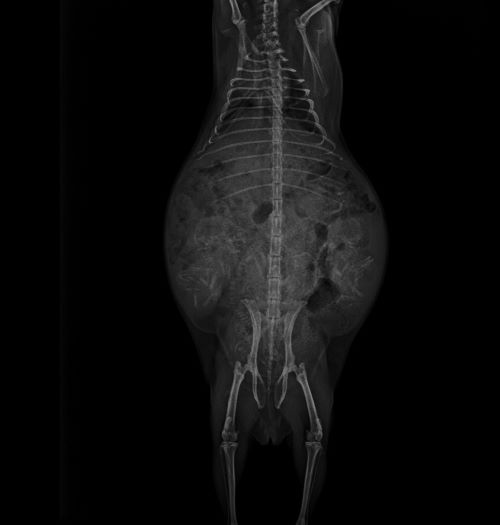

3月頃、妊娠中の「カステラ」のレントゲン写真を撮ってみると、赤ちゃんの骨が見えました!

お腹に何頭いるか分かりますか?

正解は4頭!!

赤丸の所が赤ちゃんの頭です。